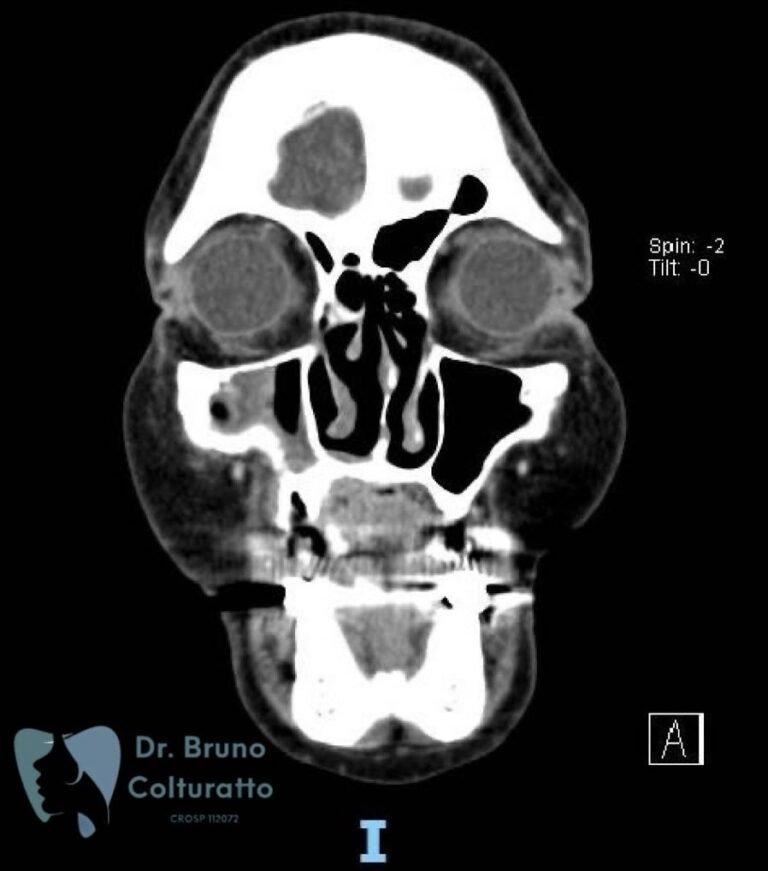

A Patologia Oral e Maxilofacial é a especialidade responsável pelo diagnóstico e tratamento de doenças que afetam a boca, mandíbula e estruturas faciais. Atua na identificação de lesões, cistos e tumores, garantindo diagnóstico preciso e tratamento adequado para preservar a saúde bucal e geral do paciente.